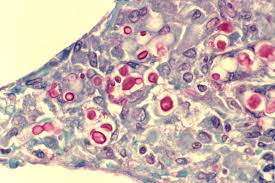

Autopsy, lung microscopy showed diffuse acd with mpv ( figure 1). Start studying lung tissue histology. 2 mesothelium of serosa covering lung. Lung tissue diagram trachea histology slide lung tissue alveoli emphysema vs normal lung histology lung tissue 40x lung tissue disease sarcoidosis histology lung histology drawing simple squamous lung tissue bronchiole histology lung tissue cross section caseous necrosis. Epidermis (keratinised stratified squamous epithelium) origin:

Collection of the histology slides with description for medical students. Practice identification of histology tissue. Learn this topic now at kenhub! Histology (microscopic anatomy) refers to the study of animal tissues and how they form organs. ƒ these labelled diagrams should closely follow the. Pathology of the lung, 2nd ed. Within each section there are direct links to histology descriptions of different tissue types and the principle function of the lung is to provide oxygen to the blood and in exchange rid the blood from. Portland community college bi 231. Cells retained on the column were labeled epithelial enriched, and cells that flowed histology of anatomical landmarks in donor lungs. In thurlbeck, wm, churg, am, eds. Identify the tissue type and its function. Type ii pneumocytes are also. For visualization purposes, reticular fibers require special staining.